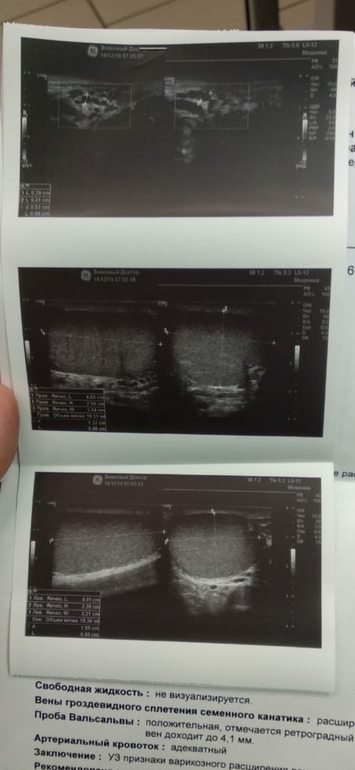

Варикоз яичка

Муж сходил на УЗИ и сдал гармоны, результат прилагаю. Вроде в рамках референсных значениях,но мне кажется или тестостерон всё-таки маленький а пролактин на верхней границе, или на это не обращать внимания? Андролог сказал что будем смотреть по гормонам, и делать вывод либо операция либо таблетками лечить варикоз. У кого у мужа так было ?